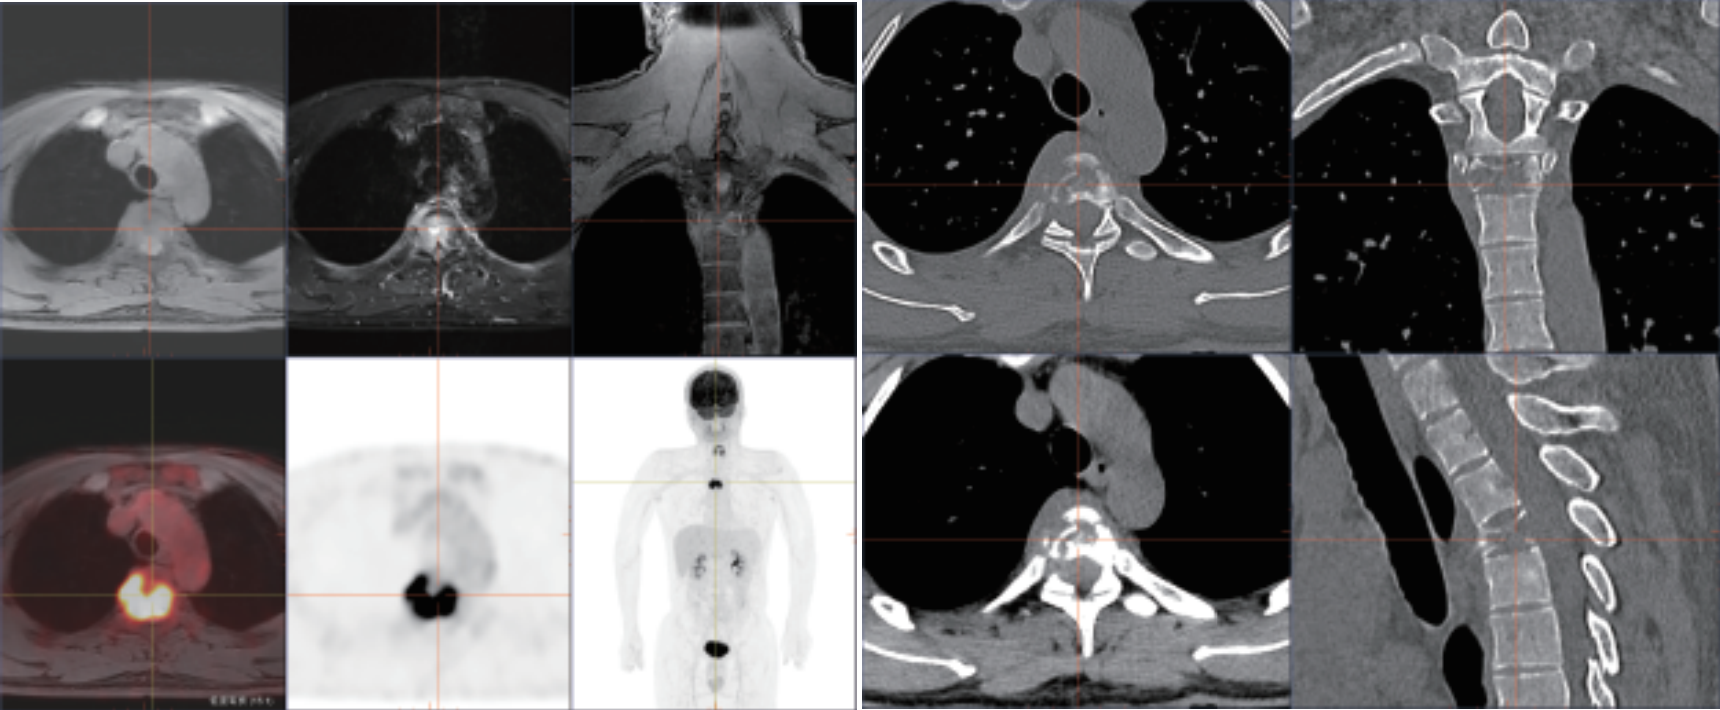

PET/MR是PET和MRI兩者融合的新型影像設備,其臨床應用具有劃時代的意義。PET/MR在腦、頭頸部、腹腔、盆腔臟器診斷效能具有明顯優(yōu)勢,廣泛應用于神經系統(tǒng)、頭頸部、胸部、乳腺、肝膽 胰脾、結直腸、生殖系統(tǒng)、血液系統(tǒng)、骨關節(jié)系統(tǒng)、不明原因原發(fā)灶腫瘤治療 前檢查、不明原因發(fā)熱、感染和嚴重性疾病的診療指導以及兒童淋巴瘤、骨肉瘤、神經母細胞瘤分期和療效評估、復發(fā)監(jiān)測和再分期。

? 強大的查體功能:PET和MRI同步掃描,MR 圖像可實現任意角度的重建和融合, 多角度的觀察解剖和代謝信息,多維度與 PET 實現軸、冠、矢三維圖像精確融合, 一次檢查便可篩查全身危險病灶,帶來更好的科研體驗。

? 小病灶高精度成像:TOF飛行時間技術精確定位真符合時間發(fā)生位置,顯著提升圖像對比度和信噪比,提供更為優(yōu)質的臨床圖像,結合3D光梭成像,可精準檢測組織微小病變,為診斷提供更為多元和準確依據。

相關病例成像圖